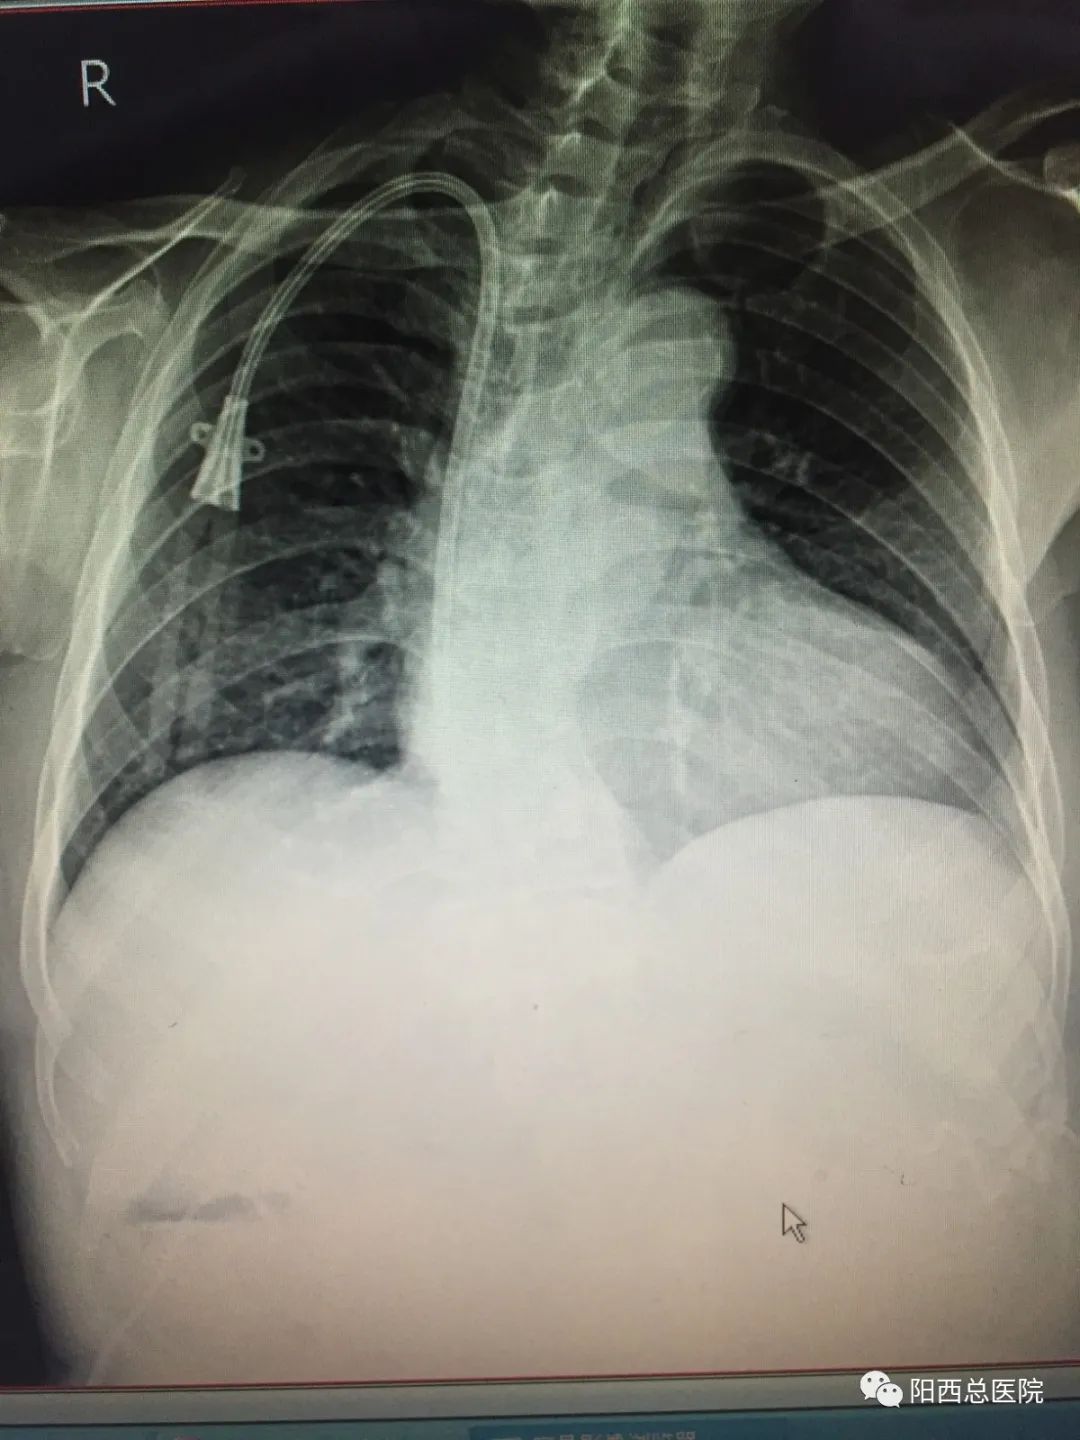

阳西总医院血液净化中心与广东省人民医院、暨南大学附属第一医院建立长期技术帮扶关系,目前可独立开展移植物内瘘成形术、X线透视下带涤纶套带隧道透析导管置管术、经皮动静脉内瘘球囊扩张术等新技术,为维持性血液透析患者的生命线提供全方位的治疗保障。